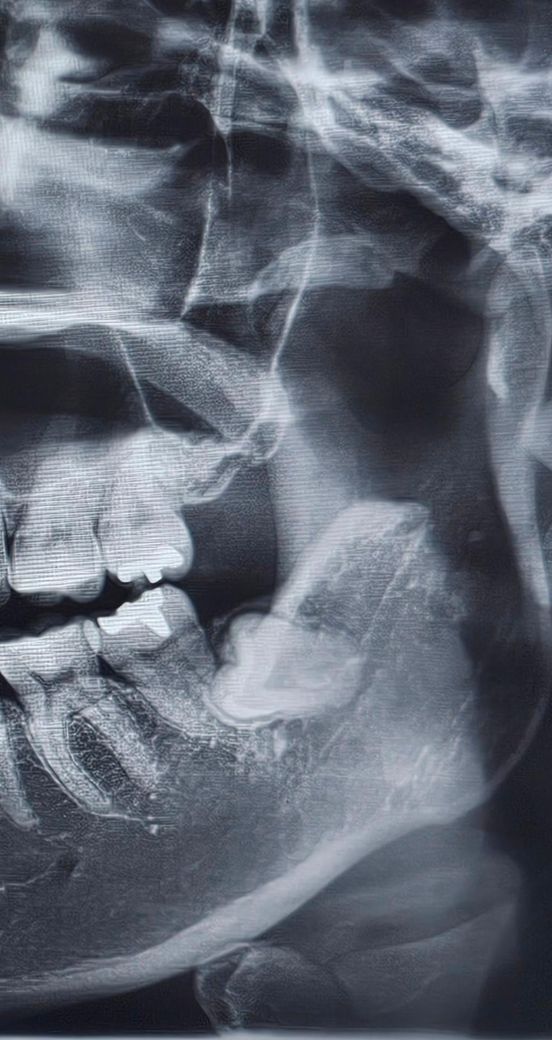

• 2번 째 사진

예방적으로 빼줘야 하는 경우는 옆 어금니와 인접하여 옆 어금니의 치아 뿌리 흡수, 충치 유발 가능성이 있을때 입니다.

지금 엑스레이상으론 근접해보이긴 하는데 정확한 건 ct를 찍어봐야 합니다.